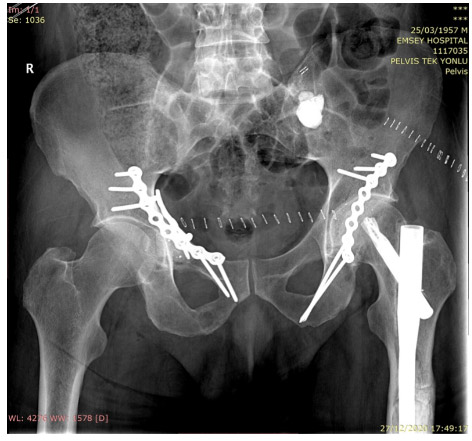

During the operation: The image shows tumor focus removal and cement application via open surgery into both acetabulums.

Post-surgery: The image shows closed cementation after RF ablation of the left pelvic bone, cementation after cleaning of metastatic foci in both acetabulums, and application of titanium plates.